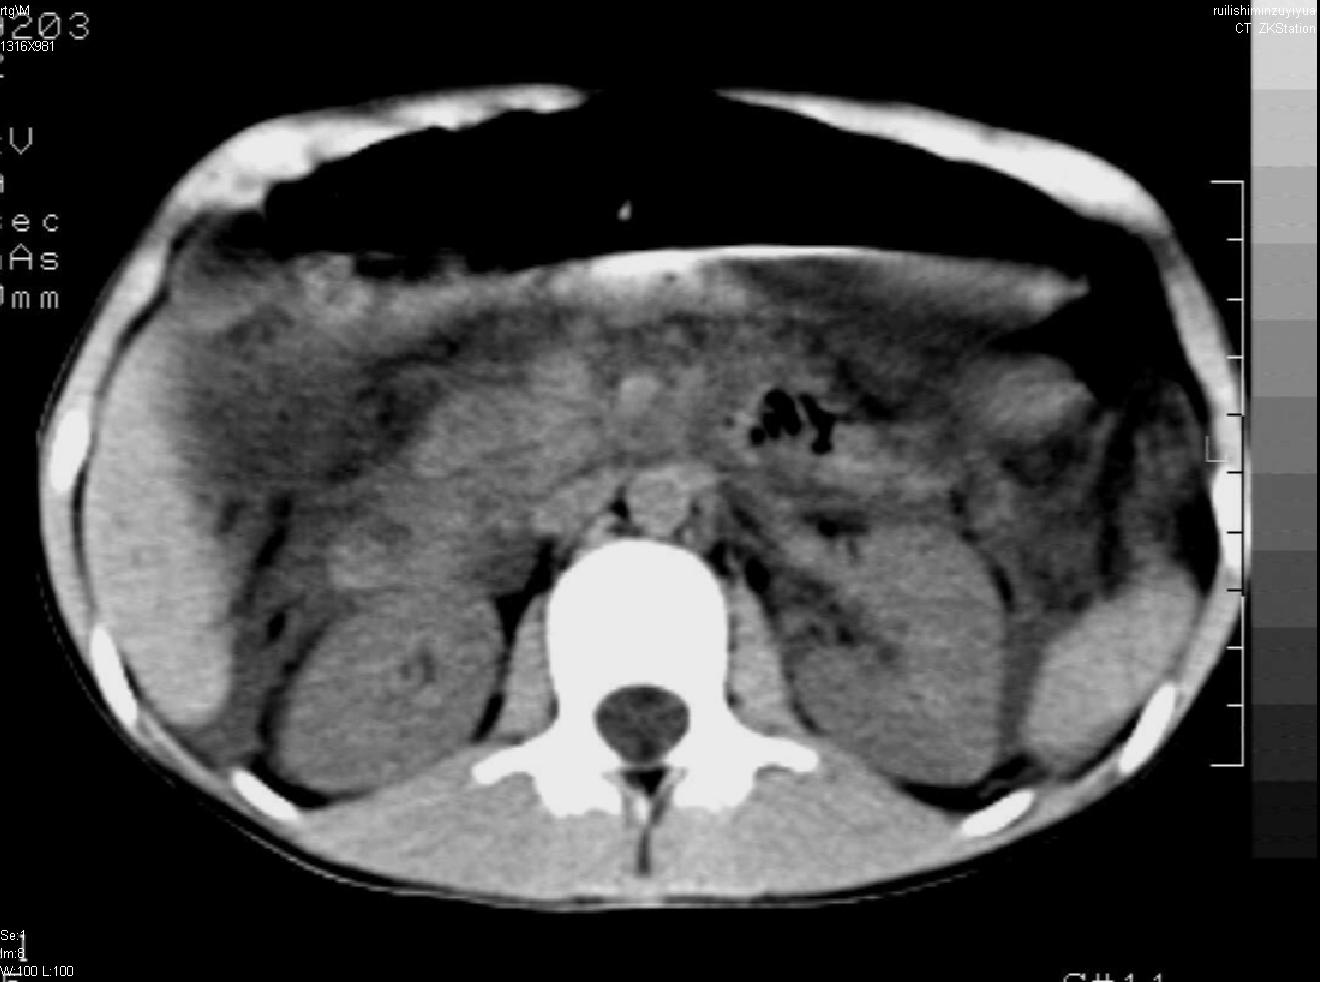

标题: PED0282:女,10岁,上腹疼痛2周 [打印本页]

标题: PED0282:女,10岁,上腹疼痛2周

b超:胆囊结石。疑坏死性胰腺炎

支持小儿急性坏死性胰腺炎。

急性胰腺炎,腹腔积液